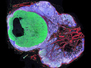

Muscle Matrix

A hydrogel mesh that protects stem cells used to boost muscle damage healing from immune attack

As a person ages their ability to repair damaged tissues dwindles in part because the number and potency of their stem cells declines. Treating an injured elderly patient with stem cells from a young healthy donor may boost the healing process, but delivering a sufficient number of cells to be effective can be difficult. The injected cells may be killed by the host’s immune system, and those that survive may drift away from the injection site. Now, researchers have developed a protective hydrogel matrix – a watery polymer mesh – that envelopes donor stem cells, keeping them in one place and preventing immune cell attack. Indeed, when such hydrogel-embedded muscle stem cells were applied to damaged mouse muscles (pictured), they led to the successful growth of new fibres (green). If such results translate to humans the approach could provide a new treatment for injuries to aged muscles or those damaged by disease.